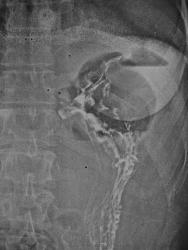

На вскидку захотелось написать - "поддиафрагмальный" абсцесс.

На обзорном - вроде уровень (абсцесс?), но с барием - деформация газового пузыря желудка?

Однозначно - поддиафрагмальный задний абсцесс.

Что-то сдается мне, что не выставил-бы банальный поддиафрагмальный абсцесс Анатолий Владимирович, да еще в конце повествование - "температура в норме". Да и фрагменты бариевой взвеси "наслаиваются" на тень "абсцесса".

Может и так. Но - "двойной" газовый пузырь желудка, причем однин из них - с уровнем жидкости. Деформация наружного контура медиального пузыря.